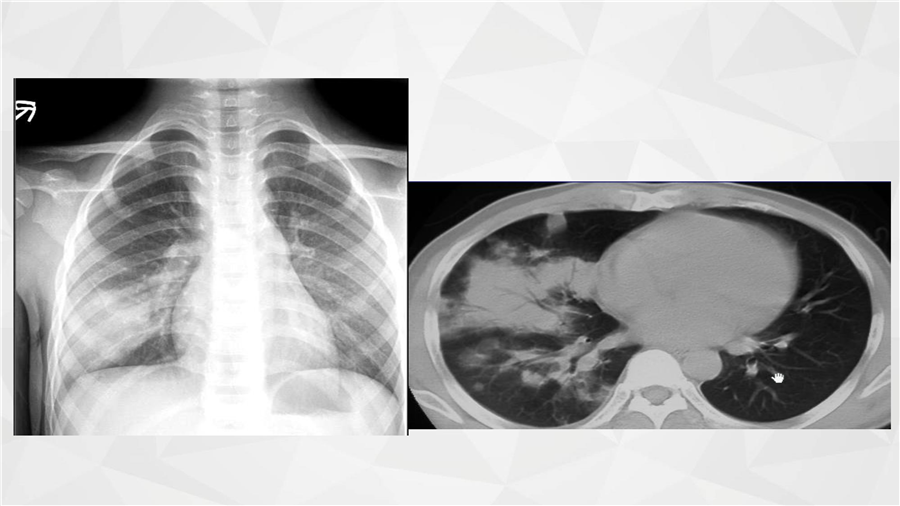

呼吸系统三